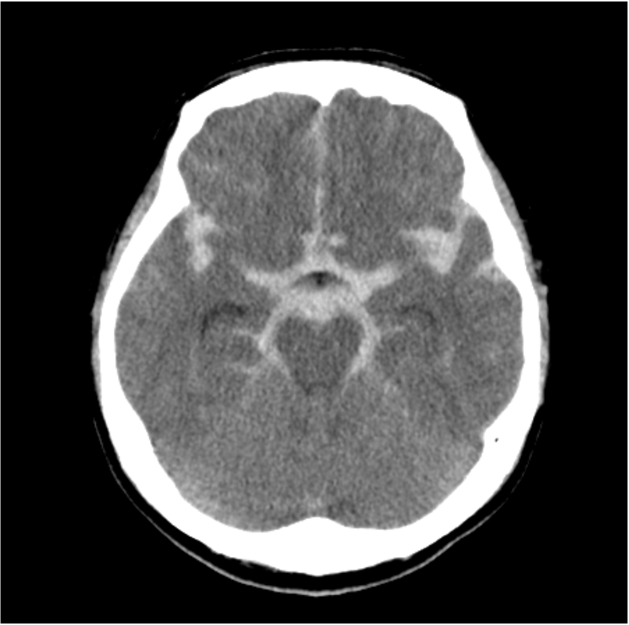

勤務中に急に意識消失し救急要請された。収縮期血圧200㎜Hgを超える高血圧も伴い、脳卒中が疑われた。頭部CTではクモ膜下腔に広範に広がる血腫を認め、くも膜下出血と診断された。前交通動脈にブレブを伴う歪な動脈瘤を認め、責任病変が疑われた。

意識障害の原因の一つとして脳卒中があり、その中の一つにくも膜下出血が含まれる。くも膜下出血の診断は単純CTで行われる。くも膜下出血の原因の多くが脳動脈瘤の破裂である。脳動脈瘤の検索にCT angiographyが有用であり、侵襲性が少なくアクセスのしやすさからも好まれる。Volume Rendering (VR) 像は全体を俯瞰でき動脈瘤を容易に認識できることが多いが、サイズや形態により動脈瘤が分かりにくいこともあるため、元画像の確認を怠らないことが大切である。また、脈瘤破裂の他、脳動静脈奇形や脳動脈解離もくも膜下出血の原因となり、これらの有無も合わせて確認する必要がある。